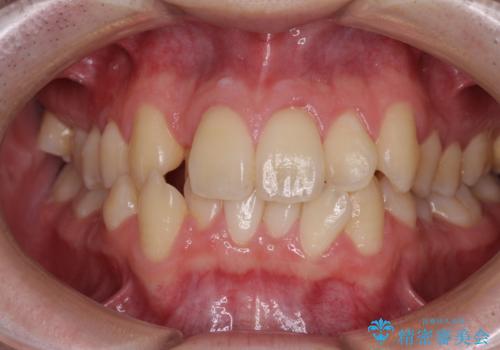

全顎的なクロスバイト 補助装置を用いてワイヤー矯正

- 八重歯や奥歯の噛みにくさを気にして来院された患者様です。

前歯のクロスバイトや八重歯の他に、左右最後臼歯のシザーズバイト(鋏状咬合)が認められました。

シザーズバイト改善のために補助装置を使用しながら、ワイヤー装置にて全体の歯列を整えることとしました。